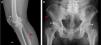

65-year old male, obese, with a history of 15 years of evolution of pain in the dorsolumbar spine and knees associated with right lower extremity paresthesia. Radiographic findings (A) right knee, bone excrescences in the patella (*) and in the fibular enthesis (red arrow), (B) ossification in enthesis of the iliac spines (red arrow) and the acetabulum. (*).